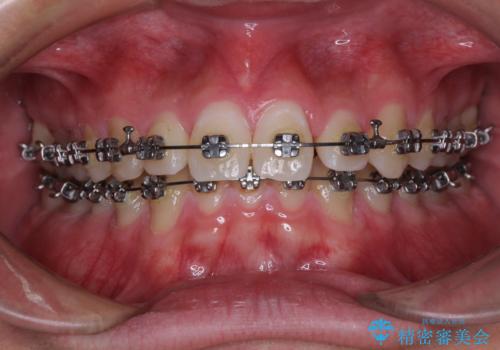

- メタルブラケット

- 1年1ヶ月

- 10-30回

ワイヤー矯正でもインビザライン矯正でも対応可能でしたが、インビザラインでの自己管理の煩わしさを避けるため、ワイヤー装置にて矯正治療を行うこととしました。

傾斜しいている大臼歯を立ち上げながら、下顎歯列を上顎に対して前方位となるように工夫し、デコボコを解消した上でディープバイトも改善することができました。